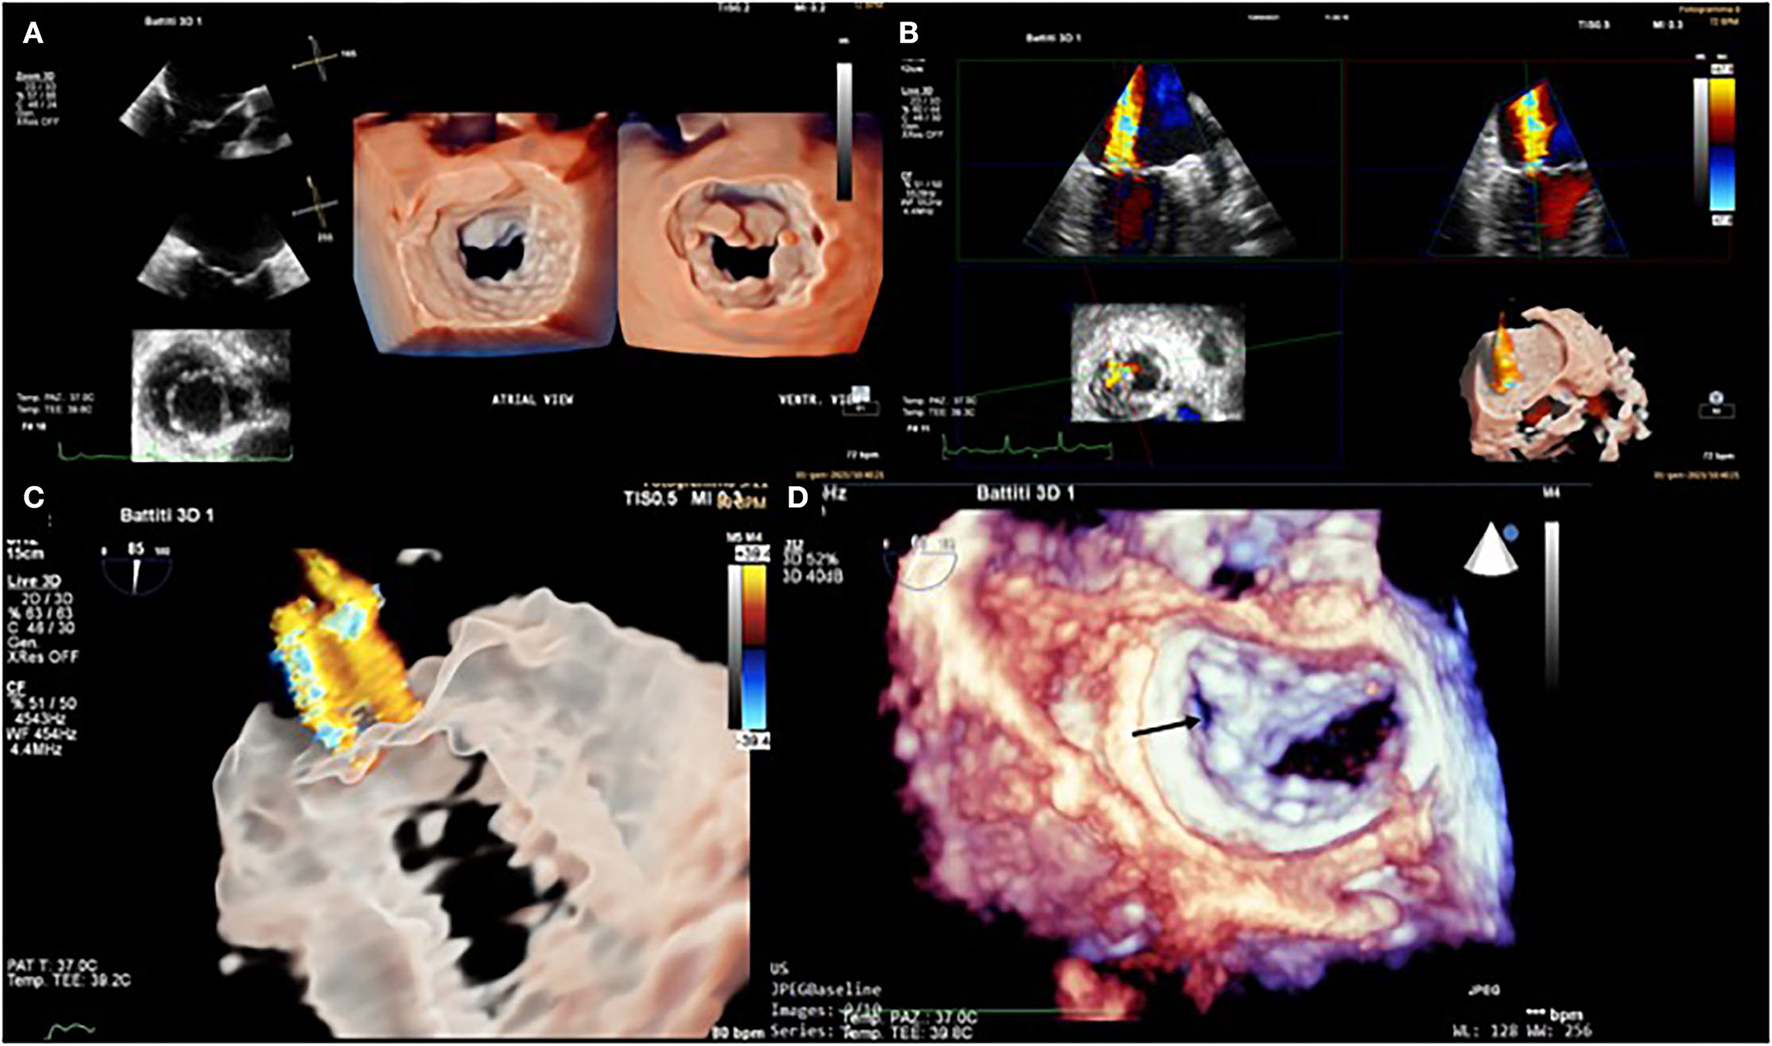

The patient selection and pre-procedural echocardiographic evaluation, in particular, to diagnose the pathoanatomic mechanism, the severity of the mitral regurgitation, the right and left ventricular size and function, the left atrial size, pulmonary hypertension, and severity of tricuspid regurgitation are crucial to identify ideal candidates for MitraClip. We describe the procedure's steps in detail, stressing the importance of collaboration between the echocardiographer and the interventional cardiologist. Two-dimensional transesophageal echocardiography (2D TEE) is the primary imaging modality for the guidance of the procedure. Realtime three-dimensional (3D) TEE has recently been introduced as an additional imaging modality (Figure 1). In comparison with 2D TEE, 3D TEE provides additional information in some procedure steps, such as precise positioning of the clip delivery system into the left atrium, and correct alignment of the clip arms perpendicular to the coaptation line, and confirmation of the right grasping location (19). Biner et al. demonstrated that using 2D and 3D TEE in combination is associated with a remarkable 28% reduction in procedure times (20). Fluoroscopy provides additional helpful information on the positioning and distance for delivery catheter advancement and MitraClip positioning. Fluoroscopy provides good spatial and temporal resolution over a wide field of view with continuous monitoring and easy identification of devices. Still, it can only provide monoplane information, does not allow visualization of soft tissue, and is related to the use of ionizing radiation and contrast medium. The two methods are therefore complementary, and the most recent innovation, such as fluoroscopic-echocardiographic fusion imaging with the new EchoNavigator (Philips Medical System, Best, The Netherlands) and TrueFusion (Siemens Healthinners, Erlangen, Germany) systems, allows simultaneous acquisition of both fluoroscopic and echocardiographic images and co-registration, thus overcoming the limitations of the two methods. The coordinates of the two images are integrated into the same reference system, thus obtaining a hybrid image, which has the advantage of being easily interpretable by the interventional cardiologist since the echocardiographic images in which the soft tissues and the functional aspect (e.g., valve regurgitation jets) are well-visualized, are integrated in real-time in the standard fluoroscopic projections where the catheters and devices are easily identifiable (21).

Figure 1

Transesophageal echocardiogram. 3D mitral valve reconstruction with atrial view (or “surgeon's view”) and ventricular view sergi (A). Severe mitral regurgitation (MR) was documented with 3D color Doppler acquisition (B). 3D Glass image of MR (C). 3D mitral valve reconstruction (atrial view) after Mitra-Clip system placement in the lateral paracommissural region (black arrow) (D).